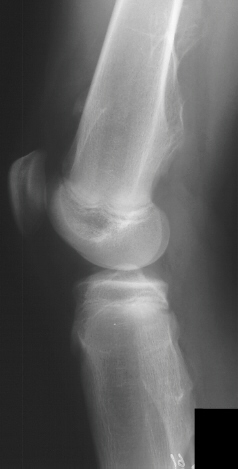

at the medial proximal tibia. X-rays of her left knee in the AP/lat/oblique

views revealed multiple exostoses of the distal femur and proximal tibia.